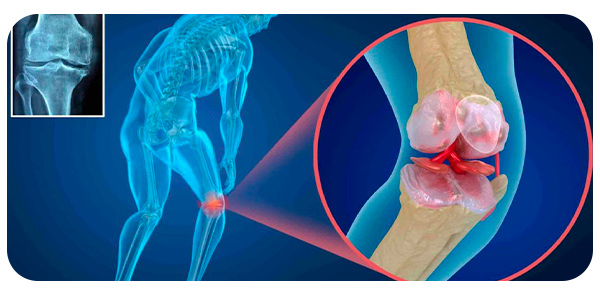

O tratamento por meio do procedimento minimamente invasiva da coluna é um procedimento que oferece mínima agressão aos tecidos do corpo. Com o mesmo objetivo da cirurgia de coluna tradicional, ela pode ser realizada através de uma pequena incisão que é restrita apenas a região doente, preservando as demais e diminuindo, em muito, o trauma cirúrgico. Além do mais, o tratamento minimamente invasivo causa menor sangramento, uma vez que preserva as funções das estruturas anatômicas.

Isso só é possível em razão do acesso às tecnologias de ponta que permitem que todo o procedimento realizado pelo neurocirurgião especializado em coluna e sua equipe, seja acompanhado por meio de microscópios ou pela técnica endoscópica da coluna.

O tratamento por meio da cirurgia minimamente invasiva da coluna é um procedimento que oferece mínima agressão aos tecidos do corpo. Com o mesmo objetivo da cirurgia de coluna tradicional, ela pode ser realizada através de uma pequena incisão que é restrita apenas a região doente, preservando as demais e diminuindo, em muito, o trauma cirúrgico. Além do mais, o tratamento minimamente invasivo causa menor sangramento, uma vez que preserva as funções das estruturas anatômicas.